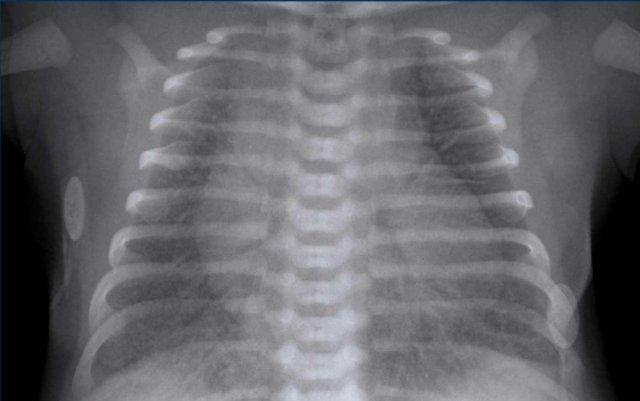

Trẻ sơ sinh 3 ngày tuổi mắc hội chứng suy hô hấp (RDS). Tuổi thai: 34 tuần.

Image

- Increased

lucency of the right pleural space. - Increased

density of the partially collapsed right lung. - Trung thất

dịch chuyển sang trái do tràn khí màng phổi có áp lực. - Pneumomediastinum

causing ‘lifting’ of the thymus.